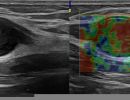

Pathologies that can be diagnosed with Peripheral Nerve Ultrasound include:

- Entrapment Syndromes (carpal tunnel syndrome, cubital tunnel syndrome, tarsal tunnel syndrome, meralgia paresthetica)

- Degenerative Changes